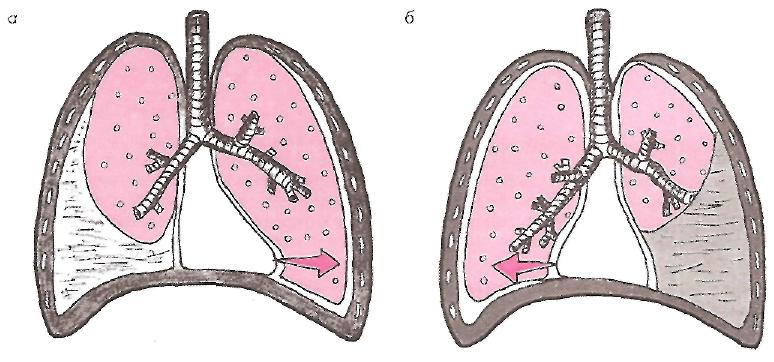

Диагностика плеврального выпота: что нужно знать